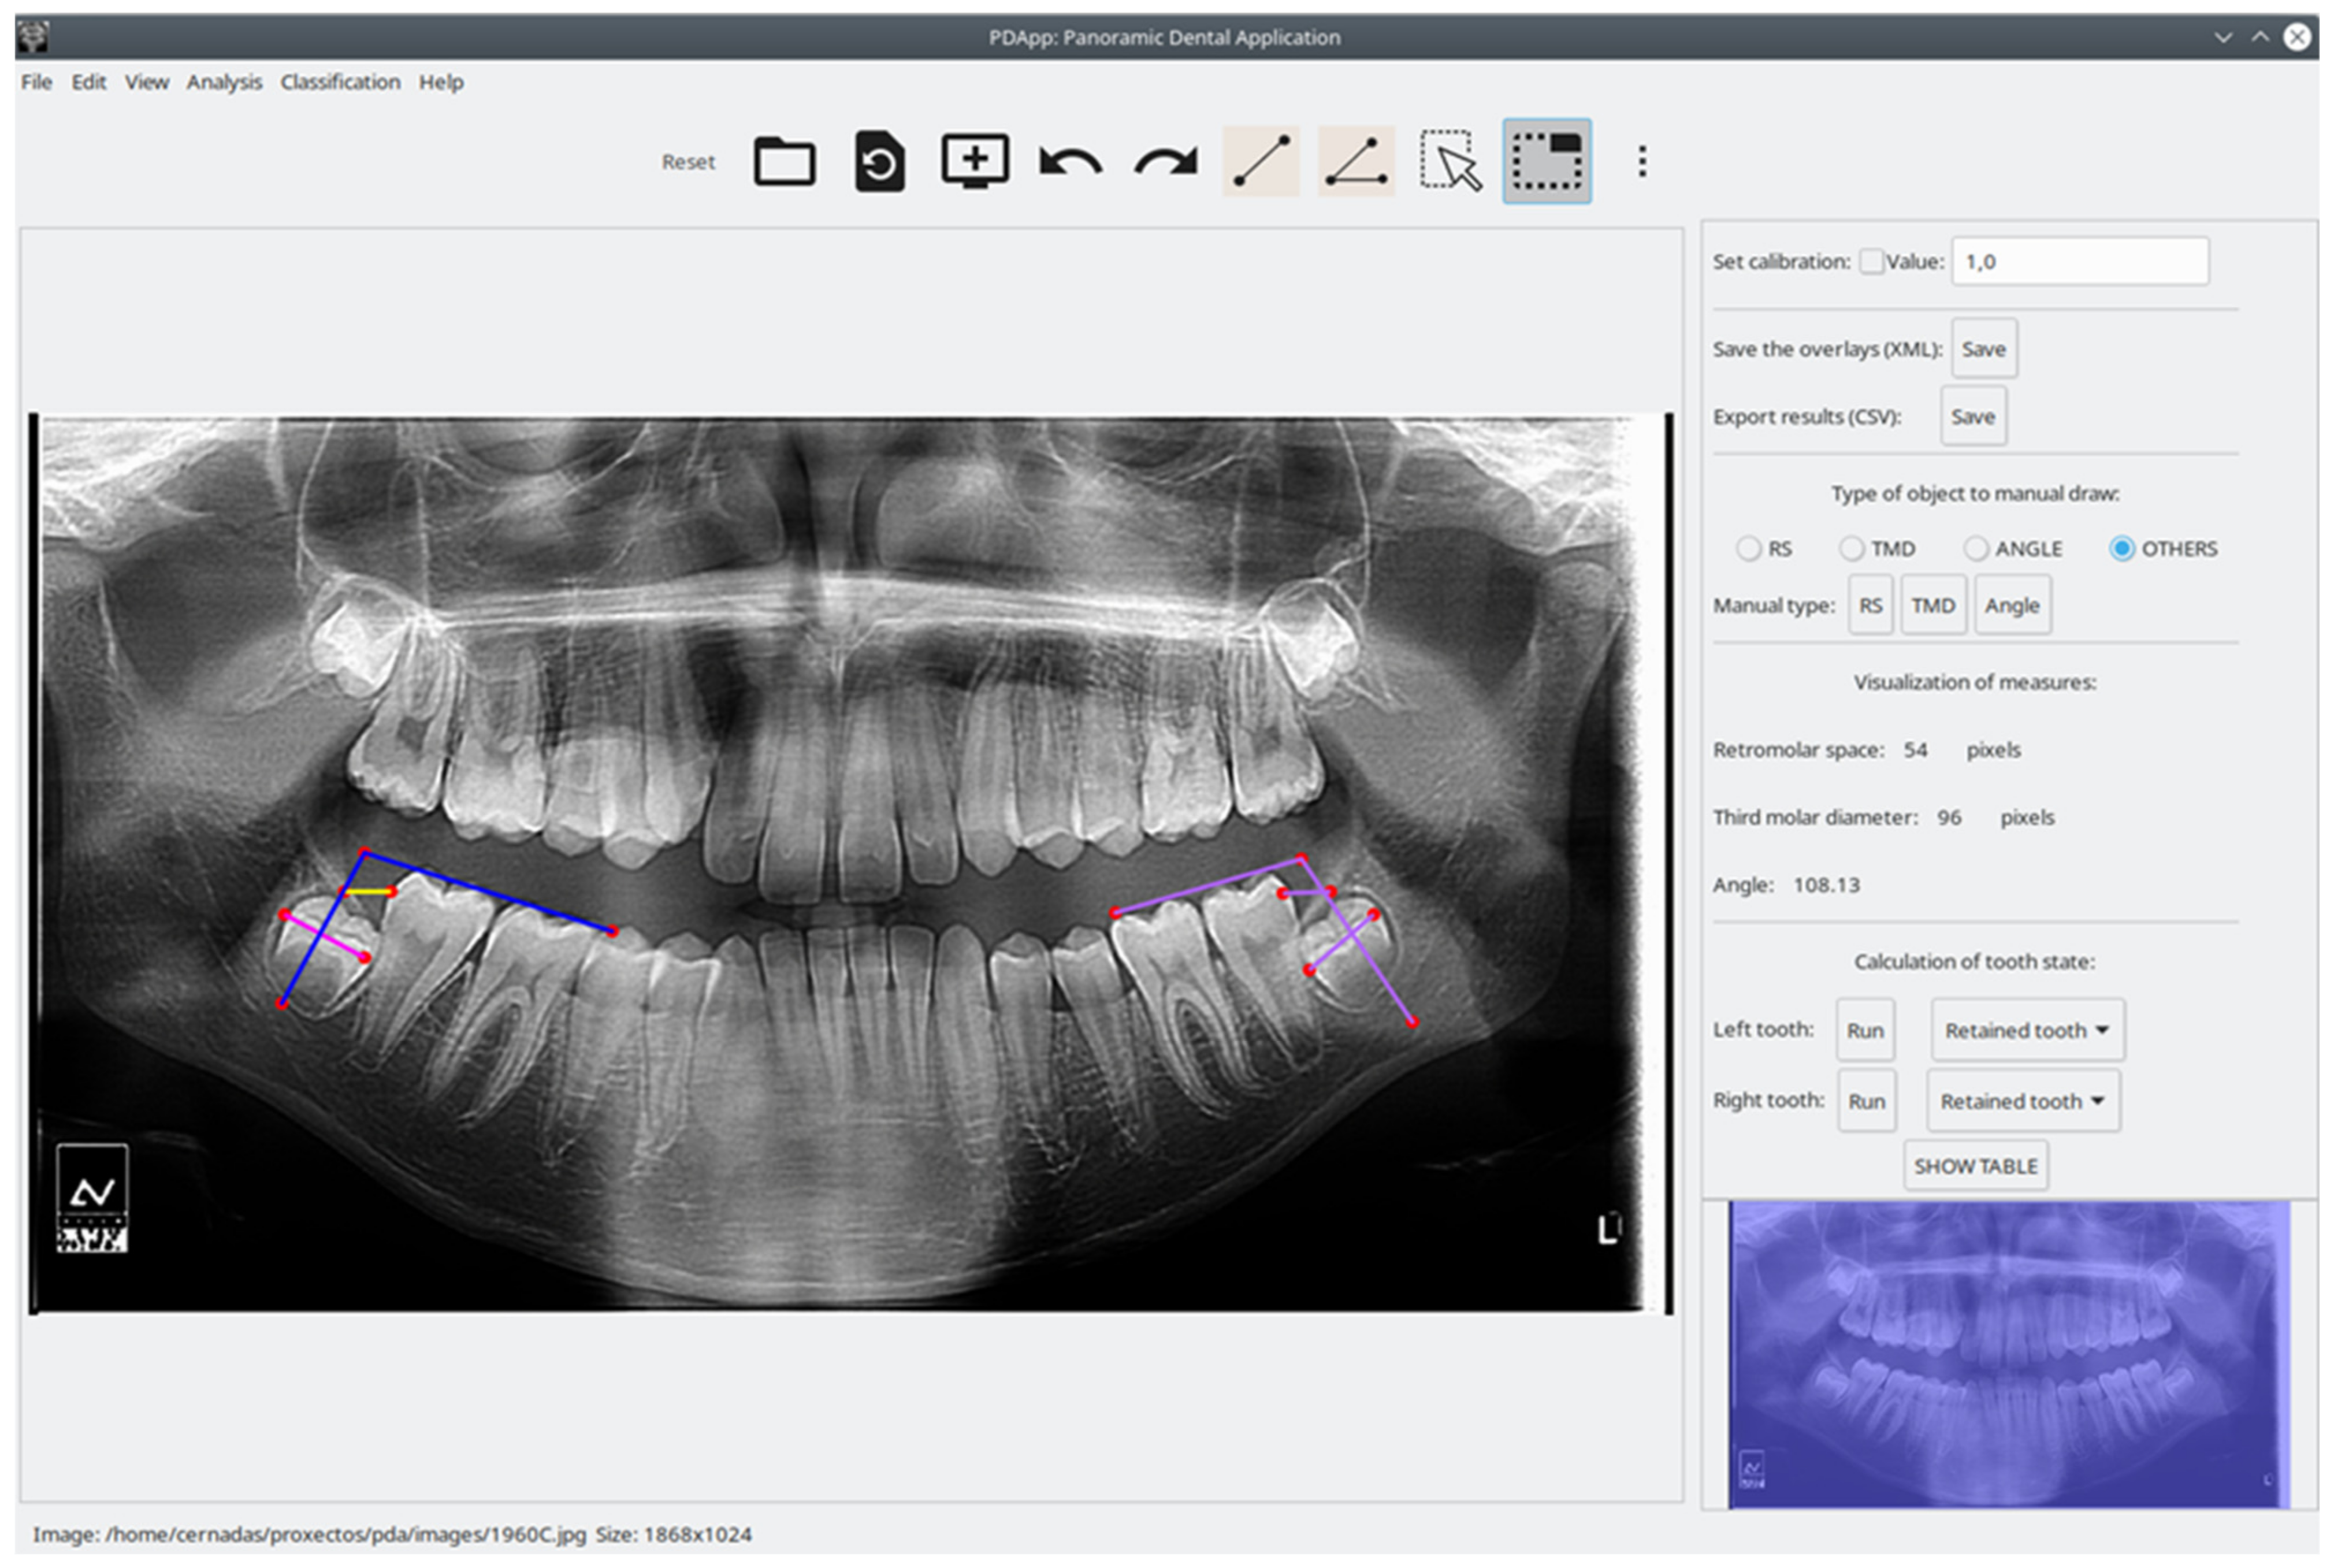

To evaluate PDApp based on operation in a real environment, the software was installed at the dental clinic of the Dentistry School of Medicine and Odontology of the University of Santiago de Compostela (Spain) in February 2021. Dental experts then used PDApp in their daily work to analyze images, which required that they manually draw the retromolar space and the third molar diameter and angle. PDApp then automatically classifies the third molars in radiological images as erupted or retained. Their operations using PDApp were logged into XML files for later statistical evaluation of the machine learning algorithm (SVM classifier) incorporated in the software. We used accuracy (rate of third molars correctly classified by the software) as a measure of the classifier performance. As mentioned, the classifier included in PDApp was initially trained using a dataset of 188 molars. Thereafter, PDApp was used to classify 539 third molars from 289 patients, and 97.96% of third molars were correctly classified. Figure 3 shows an example of correct classification of the third molar by PDApp as retained. Figure 4 shows a case of a third molar that is classified as erupted by PDApp.

Figure 4. Visual example of a third molar erupted, predicted correctly by PDApp. The pink line represents third molar diameter, the yellow line represents retromolar space, and blue lines represent the angle of eruption.